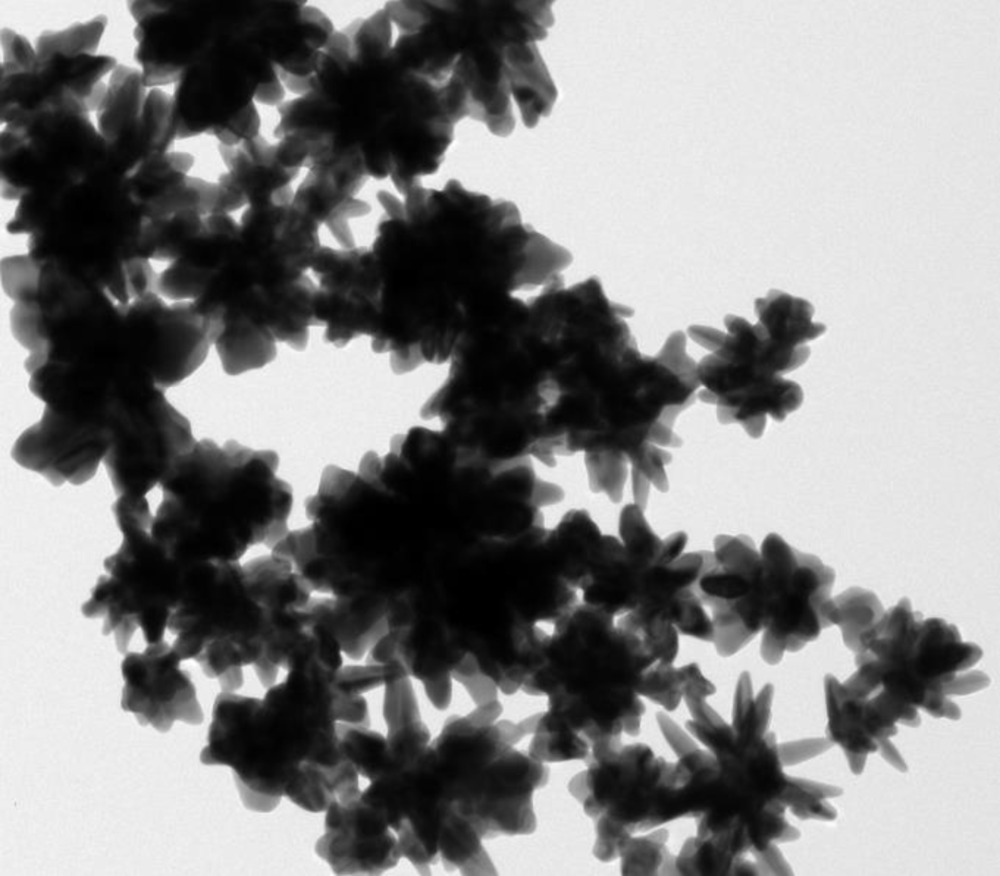

Ученые из Национального технологического университета «МИСиС» (Москва, Россия) совместно с коллегами из Института ядерной физики имени Саха (Калькутта, Индия) смогли синтезировать стабильные золотые наночастицы в форме звезд для борьбы с онкологическими заболеваниями. Недорогие и нетоксичные наночастицы позволят эффективно диагностировать рак на ранних стадиях и точечно уничтожать пораженные клетки. Результаты исследования опубликованы в научном издании Journal of the Chemical Society.

Сегодня в медицине активно используются плазмонные наноматериалы на основе серебра и золота. «Плазмонными» называют наноструктуры, необычные оптические и физические свойства которых обусловливаются прежде всего их формой и структурой, а также колебанием свободных электронов внутри них. То, каким образом происходит это колебание, сильно зависит от формы и размера наночастиц. Именно это позволяет им иметь набор необычных оптических и физических свойств.

Такие наночастицы имеют широкое биомедицинское применение — они используются в геномике, биосенсорике, иммуноанализе, лазерной фототерапии раковых клеток, адресной доставке лекарственных препаратов, ДНК и антигенов, биоимиджинге и мониторинге клеток и тканей. Однако у плазмонных наночастиц на основе золота есть существенный недостаток: при введении в кровь они начинают агрегировать (слипаться) под воздействием слишком большой для них концентрация хлорида натрия. Таким образом сосуды засоряются, и доставить наночастицы к пораженным тканям становится невозможно.

«Ученые Центра энергоэффективности НИТУ „МИСиС“ под руководством профессора Дулала Сенапати из Института ядерной физики имени Саха смогли решить проблему доставки наночастиц к пораженным тканям. Они синтезировали стабильные наночастицы на основе золота, которые не слипаются при введении в кровь, и обладают высокой эффективностью в спектроскопии комбинационного рассеяния», — отметила ректор НИТУ «МИСиС» Алевтина Черникова.

Молекулы на поверхности наночастицы из золота значительно усиливают сигнал комбинационного рассеяния — при свечении лазера наблюдается обратное яркое свечение наночастиц.

У каждой молекулы есть так называемая «область отпечатков пальцев». Данная область специфична для молекул разного типа и обычно плохо видна, так как она слабая. Именно наночастицы из золота способны приумножить данный сигнал во много раз и ярко светятся при скоплении даже небольшого количества молекул, поэтому с их помощью можно диагностировать рак на более ранних стадиях.

Специалисты синтезируют золотые наночастицы в водном растворе с использованием витамина C, поэтому они нетоксичные и недорогие. По предварительным оценкам, себестоимость раствора объемом 100 микролитров составляет около 50 рублей.

Работа над технологией проводилась при участии специалистов Российского онкологического центра имени Н.Н. Блохина. Сейчас ученые работают над улучшением частиц — пытаются синтезировать другие типы звезд.